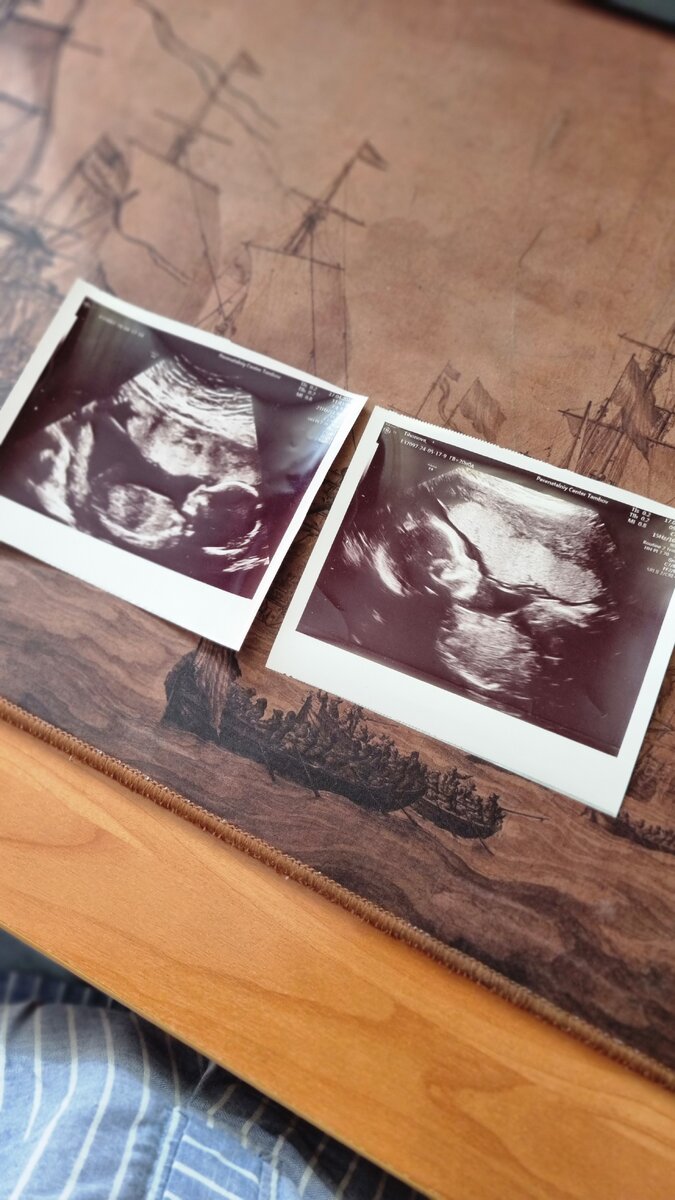

Я тут на УЗИ с мужем ездила и узнавала пол ребёнка.

Представляете, срок моей беременности уже дошёл до полных двадцати недель! А это значит то, что мы точно прошли полпути. Просто удивительно, как быстро летит время! Не успею оглянуться, а уж и рожать пора придёт.

На таком сроке обычно делается второй скрининг. Идёт проверка буквально всего. Доктор даже пальчики у нашего ребёночка пересчитывал.

Когда мы приехали с мужем на УЗИ, то сразу попросили врача не сообщать нам пол ребёнка, а написать его на бумажке. Доктор выполнил нашу просьбу. Он протянул нам в четверо сложенный листок бумаги с этой ценной информацией, и мы тут же спрятали его в конверт, который отдали на хранение хорошей знакомой, чтобы не узнать до поры, до времени, кого ждём.